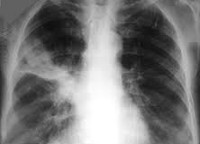

Поскольку клинические признаки инфильтративного туберкулеза легких малоспецифичны или отсутствуют совсем, основное значение в диагностике имеют объективные, инструментальные и лабораторные данные. Аускультативная картина характеризуется наличием звучных хрипов; перкуссия обнаруживает притупление звука над областью инфильтрата. Особенно эти изменения выражены при лобите и наличии распада инфильтрата с формированием каверны. Воспалительные изменения крови (сдвиги в лейкоформуле, ускорение СОЭ) незначительны.

Туберкулиновая проба у больных инфильтративным туберкулезом легких чаще положительная. Рентгенография легких позволяет не только обнаружить инфильтративные изменения, но и оценить характер тени, проследить динамику лечения. Выявить МБТ можно как с помощью микроскопического исследования, так и методом бактериологического посева мокроты или смывных вод бронхов, полученных при проведении бронхоскопии.

• Облаковидный инфильтрат. Рентгенологически определяется в виде слабоинтенсивной гомогенной тени, имеющей расплывчатые контуры. Имеет склонность к быстрому распаду и формированию свежих каверн.

• Круглый инфильтрат. На рентгенограммах имеет вид округлого гомогенного фокуса (иногда с участком распада в виде просветления) с четко очерченными границами; чаще локализуется в подключичной области.

• Дольковый (лобулярный) инфильтрат. При рентгеновском исследовании выявляется негомогенное затемнение неправильной формы, образованное слиянием нескольких очагов, часто с распадом в центре.

• Краевой инфильтрат (перисциссурит). Обширная облаковидная инфильтрация, снизу ограниченная междолевой бороздой. Имеет треугольную форму с углом, обращенным в сторону корня легкого, а основанием - кнаружи. Нередко возникает поражение междолевой плевры, иногда с развитием туберкулезного плеврита.

• Лобит. Обширный инфильтрат в легком, занимающий целую долю. Рентгенологически характеризуется негомогенным фокусом с наличием в нем полостей распада.